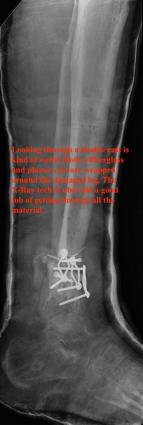

Post-corrective surgery X-Rays of the damaged right & left legs / ankles

The first two x-rays show Liam’s left ankle and pelvis prior to the accident. For comparison purposes it is interesting to see the

differences. The next x-rays were taken after the corrective surgery performed by Dr. Armendariz. Noticed that Dr. Armendariz has used tibia

bracing and also aligned the bone fragments of the left leg so that they could heal in the proper orientation. The external fixation has been

removed and Liam’s left foot has been returned to a more natural alignment.